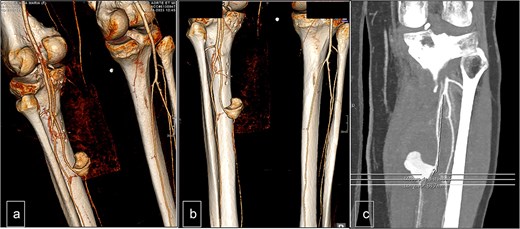

The Doppler ultrasonography was supplemented with contrast-enhanced computed tomography (CT angiography) and 3D reconstructions. The CT scan identified a hematoma with a pseudoaneurysm located at the inferior aspect, measuring 28 mm in height, 29 mm in the transverse axis, and 20 mm in the anteroposterior axis. The lesion was supplied by the PTA, which flowed laterally to the pseudoaneurysm. The medial wall of the PTA appeared discontinuous over a length of ~6 mm (Fig. 2).

Computed tomography. (a) Lateral view, (b) posterior view, and (c) vascular reconstruction. The medial wall of the posterior tibial artery appeared discontinuous over a length of ~6 mm.